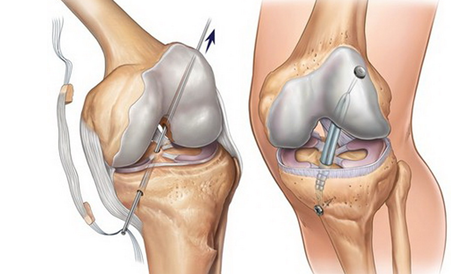

Реконструкция передней крестообразной связки: возвращение к активной жизни

Если разрыв связки мешает вам жить и заниматься спортом, современная хирургия предлагает эффективное решение. В статье подробно описаны все этапы реконструкции передней крестообразной связки, от выбора метода до полного восстановления.